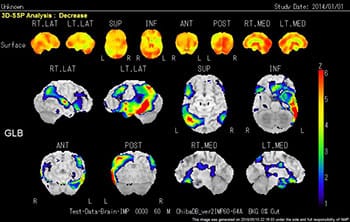

当院では、Cannon社製SymbiaE装置2台が稼働しています。主に骨シンチや負荷心筋シンチの検査ですが、他にもさまざまな検査を行っています。今後の高齢化社会に向けて認知症の診断は増加傾向にあります。アイソトープ検査は体内の様々な臓器の機能画像を得るために放射性医薬品を用います。検査の注意事項はお渡しする検査予約票に記載されていますのでご確認して下さい。当院では、がん治療のアイソトープ内用療法も行っています。

脳の血流(十分な酸素やブドウ糖を届けるため)を評価する検査です。脳の血流は脳梗塞など脳血管の要因のみならず、アルツハイマー型認知症などの脳の変性疾患でも低下することが知られており、画像解析(3D-SSP解析、局所脳血流解析)で認知症の早期発見や鑑別診断、進行度の評価を行います。